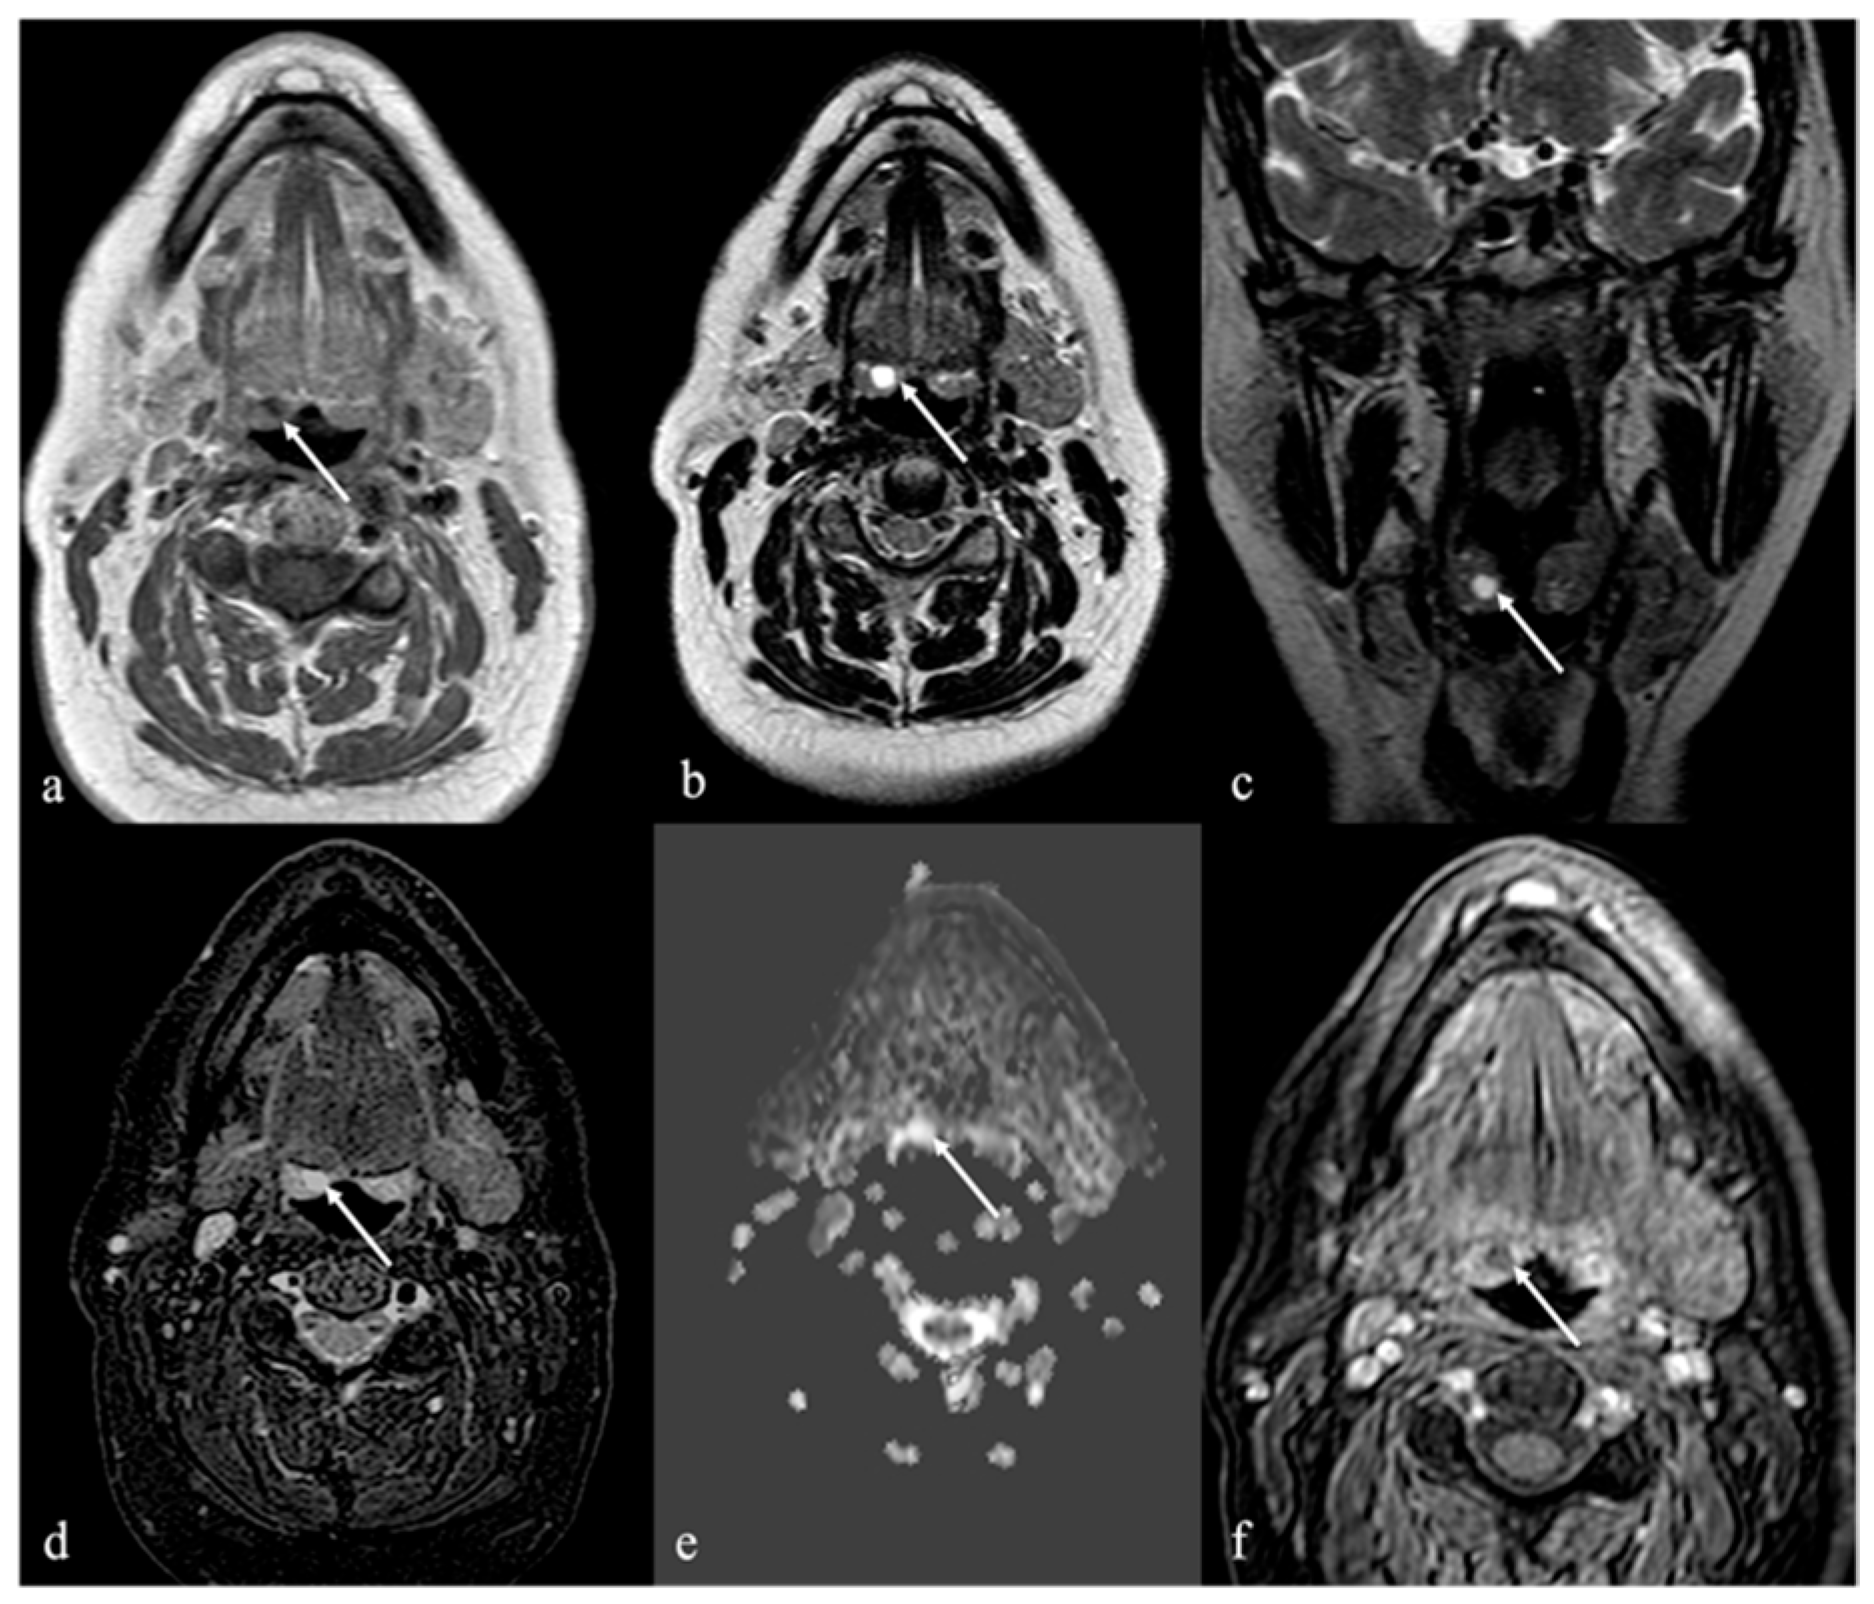

3. Schwannoma

5. Vascular Malformations and Tumors

5.1. Venous Malformations

5.2. Lymphatic Malformations

| Schwannoma [6,7] | CT: hypodense MRI: high T2 SI, split fat, target and fascicular signs | Venous malformation, dermoid cysts, lipoma |

| Venous malformation [1,9] | CT: phleboliths MRI: high T2 SI, +CE | Other vascular malformations, schwannoma, dermoid cysts |

| Lymphatic malformation [10,11] | Unilocular or multilocular, microcystic (<1 cm) or macrocystic (>1 cm) CT, MRI: no solid nodule with +CE MRI: high T2 SI, fluid-fluid levels | Other vascular malformations, dermoid cysts |